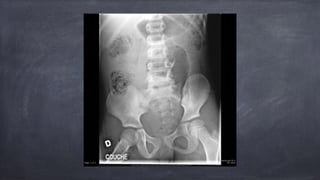

• 24.

Rupture vésicale extrapéritonéale 90-100% de cas sont associées à des Fx bassin surtout de l’arche antérieur du pubis parfois par spicules osseux pas toujours même force déchirante entre fixité du bassin et inertie d’une vessie

• 25.

Rupture vésicale extrapéritonéale Cystographie Extravasation de contraste à la base de la vessie espace périvésical aspect en flammes, en plumes, « starburst » vessie en forme de larme/teardrop Peut extravaser vers cuisse, périné, OGE, paroi abdo

• 26.

Rupture vésicale intrapéritonéale Déchirure horizontale large dans le dôme vessie portion de la vessie moins « soutenue » seule portion de la vessie adjacente/couverte par péritoine plus grande proportion antan chez l’enfant

• 27.

Rupture vésicale intrapéritonéale urine se déverse dans la cavité péritonéale délais possibles dans le diagnostic anomalies électrolytiques fausse anurie

• 28.

Rupture vésicale intrapéritonéale Cystographie Extravasation dans la cavité péritonéale Contraste le long des anses dans les gouttières paracoliques sous le diaphragme

• 29.

Rupture vésicale combinée(extra & intrapéritonéale) Cystographie Extravasation dans la cavité péritonéale Extravasation dans l’espace périvésical Habituellement avec trauma pénétrant